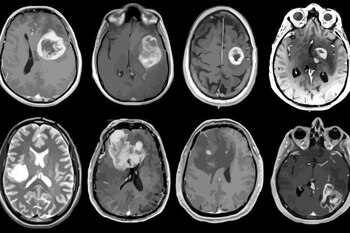

Los investigadores probaron su dispositivo en seis pacientes sometidos a cirugía cerebral para extirpar un tumor de glioma, los cuales afectan al cerebro o a la médula espinal, y se cuentan también entre los cánceres cerebrales más mortíferos debido a que son especialmente difíciles de tratar.